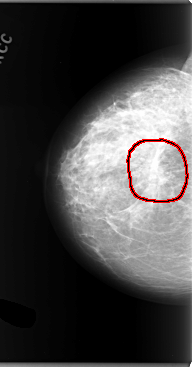

C_0101_1.RIGHT_MLO

FILE: C_0101_1.RIGHT_MLO.OVERLAY

TOTAL_ABNORMALITIES 1

ABNORMALITY 1

LESION_TYPE MASS SHAPE ARCHITECTURAL_DISTORTION MARGINS ILL_DEFINED

ASSESSMENT 5

SUBTLETY 5

PATHOLOGY MALIGNANT

TOTAL_OUTLINES 1

BOUNDARY